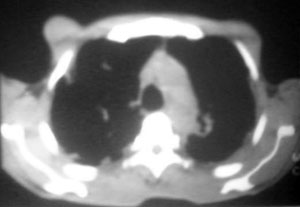

以下是引用逸风在2006-9-12 14:57:00的发言:[br]ct显示双肺上叶点片状及纤维索条状密度不均影,肺野外带近胸膜可见大小不等的含气空腔,壁略厚,境界清晰,未见液平面,中下肺野散在小片状及点状高密度影;纵隔内显示点状钙化,未见明显淋巴结肿大,构成胸廓诸骨未见明显异常.[br]诊断意见:1.双肺结核合并支气管播散;2.双肺上肺大泡.